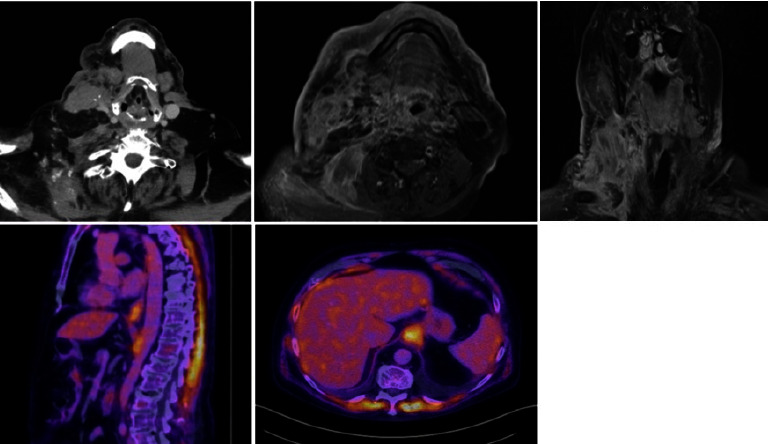

Dermal metastasis is a rare manifestation of visceral disease, and esophageal adenocarcinomas represent around only 1% of primaries that present with cutaneous metastasis. In this case, we discuss a patient who presented with a painless submental mass and extensive right neck cutaneous induration and erythema. Core needle biopsy demonstrated poorly differentiated adenocarcinoma. Blood testing also demonstrated elevated carbohydrate antigen 19-9, carcinoembryonic antigen, and alkaline phosphatase. PET/CT followed by esophagoscopy led to the diagnosis of esophageal signet-cell adenocarcinoma primary with isolated dermal metastasis. The patient was started on palliative radiotherapy and passed away two months later from a suspected thoracic fistula and hydropneumothorax.

Abstract Image